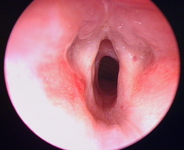

Laryngeal appearance after supraglottoplasty using cold steel

From the personal teaching collection of Simone J. Boardman, MBBS, FRACS (OHNS) and C. Martin Bailey, BSc, FRCS, FRCSEd